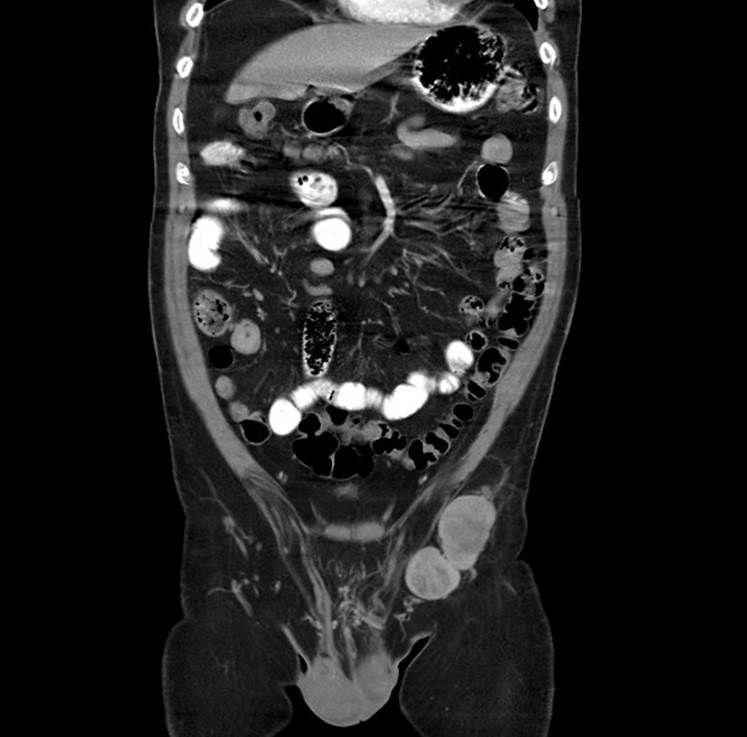

Dentro del seguimiento se observa aumento de volumen a nivel inguinal izquierdo a los 6 meses. Se realiza tomografía abdominopélvica, (Fig. 6) evidenciando patología a nivel inguinal izquierdo. Es valorado por cirugía oncológica ofreciendo lifandectomía con fines de estatificación. El paciente no acepta procedimiento quirúrgico por lo que se envía a oncología médica, iniciando tratamiento paliativo con temozolamida. Persiste con progresión de la actividad tumoral a nivel hepático, esplénico y ganglionar inguinal izquierdo. Nuevo estudio de tomografía evidencia progresión en el número y tamaño de las metástasis hepáticas y esplénicas, se identifican metástasis óseas; lesiones blásticas a nivel de L4, T7 y T9. Oncología medica cambia a tratamiento paliativo con INF alfa 2b y ácido zoledrónico. Finalmente, el paciente fallece 16 meses después del diagnóstico secundario a falla hepática y falla renal.